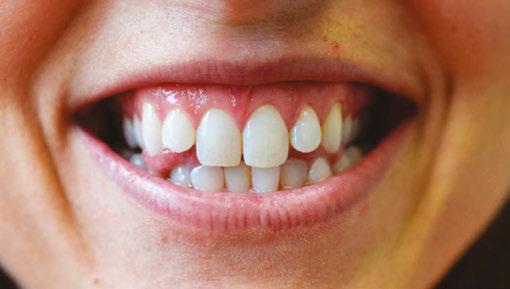

Patient J, a 39-year-old female, (Figures 1, 2, 3, 4, 5, 6) came to the office with concerns about difficulties chewing food and experiencing dry mouth upon waking up in the morning. Additionally, her partner was disturbed by her snoring. Upon examination, several issues came to light:

1. An open bite in the anterior region and a posterior crossbite

2. Breathing through the nose 10% of the time.

3. Lips and cheek muscles actively helping with swallowing food and drinks

4. Lips open 100% of the time

5. Tongue cannot maintain position on a spot, moves between teeth upon swallowing

6. Tongue thrust

7. Weak control over soft palate

Muscle tension around the temporomandibular joint (TMJ) was also evident5 as well as mandibular bilateral lingual torus as response to constant occlusal pressure applied during bruxism.

Figure 1: Swallowing with tongue trust

Figure 2: Anterior view before treatment

Figures 3 and 4: 3. Right side before treatment. 4. Left side before treatment

Figures 5 and 6: 5. Upper arch before treatment. 6. Lower arch before treatment